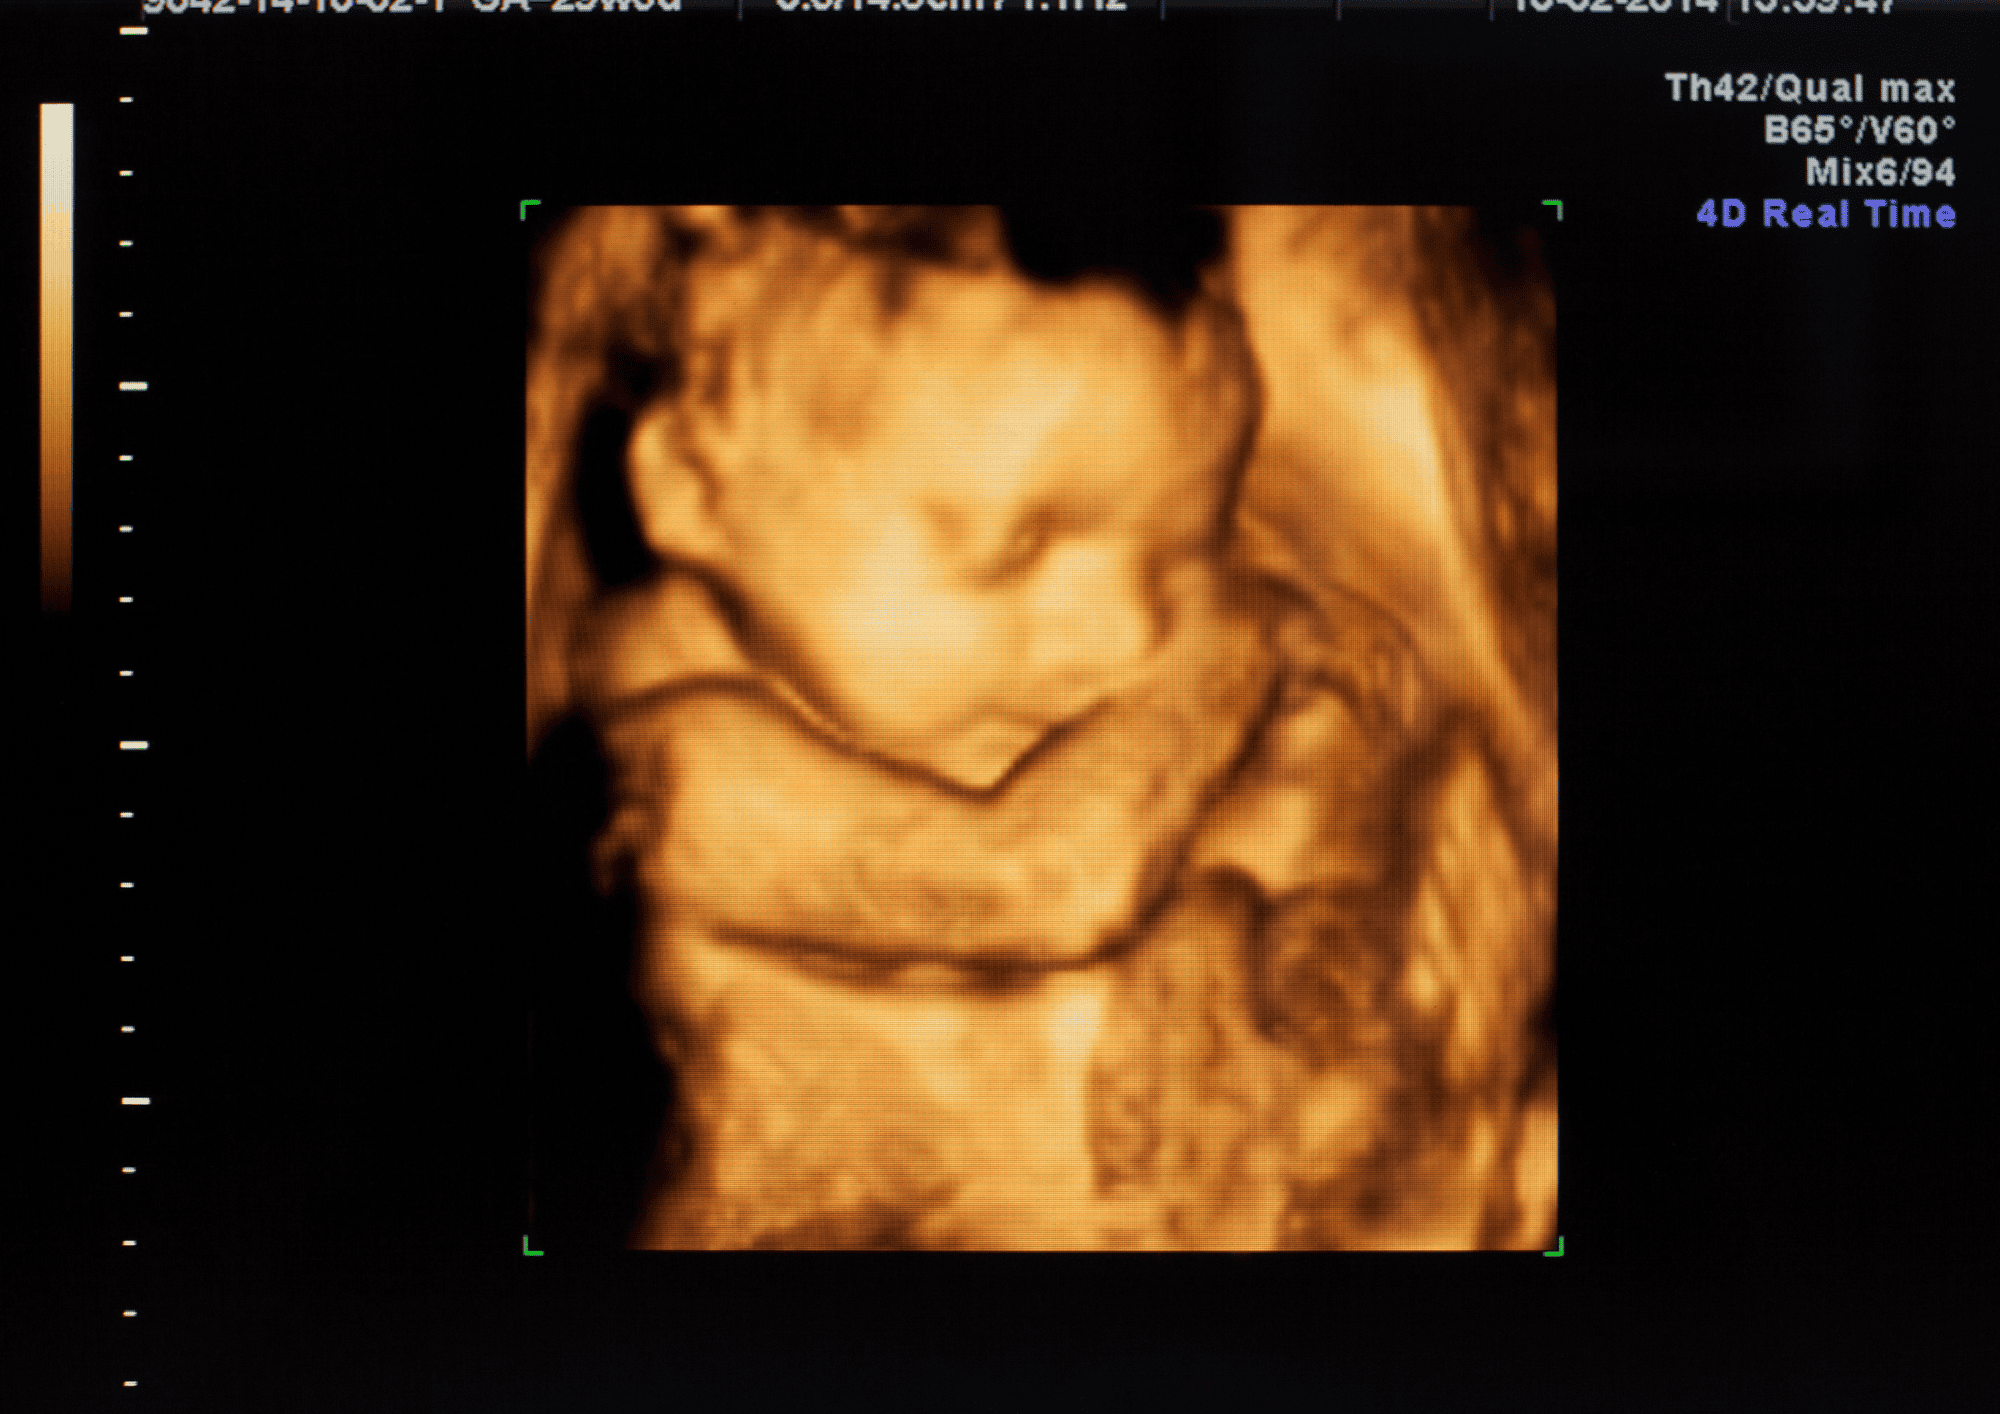

Těhotenství je obdobím plným radostného očekávání, ale zároveň přináší fyzické a hormonální změny, které mohou výrazně ovlivnit energii nastávající maminky. Únava v těhotenství je zcela normální, ale ...